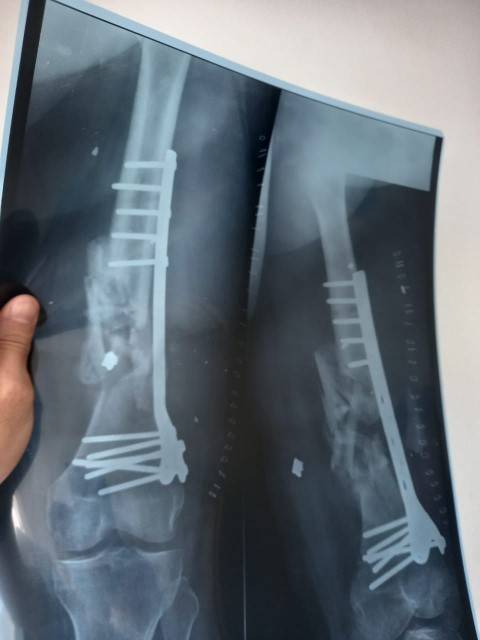

في إطار الجهود التي يقدمها المستشفى من أجل تقديم الخدمة والرعاية الطبية والإنسانية للأهل في قطاع غزة، أجرت طواقم المستشفى الميداني الأردني غزة /78 أمس السبت، عملية جراحية لتثبيت كسر مفتوح في أسفل عظم الفخذ (DISTAL FEMUR FX ORIF).

من جانبه بين طبيب جراحة العظام والمفاصل أن المريض كان يعاني من كسر مفتوح في أسفل عظم الفخذ اليمين مما أدى إلى تفتت العظم وتهتك الأنسجة المحيطة به نتيجة الإصابة التي تعرض لها المريض، وتم إجراء عملية جراحية وتركيب صفيحة معدنية وبراغي وإزالة المثبت الخارجي في المستشفى الميداني الأردني لكونه المستشفى الوحيد الذي ما زال مستمراً شمال القطاع.